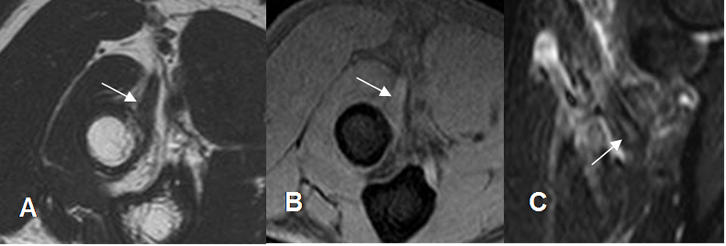

Fig 51. Tendinitis del bíceps.

A: RM axial en T2, B: RM axial en GE y C: sagital en STIR. Aumento en la señal sobre la inserción del tendón, por tendinitis.